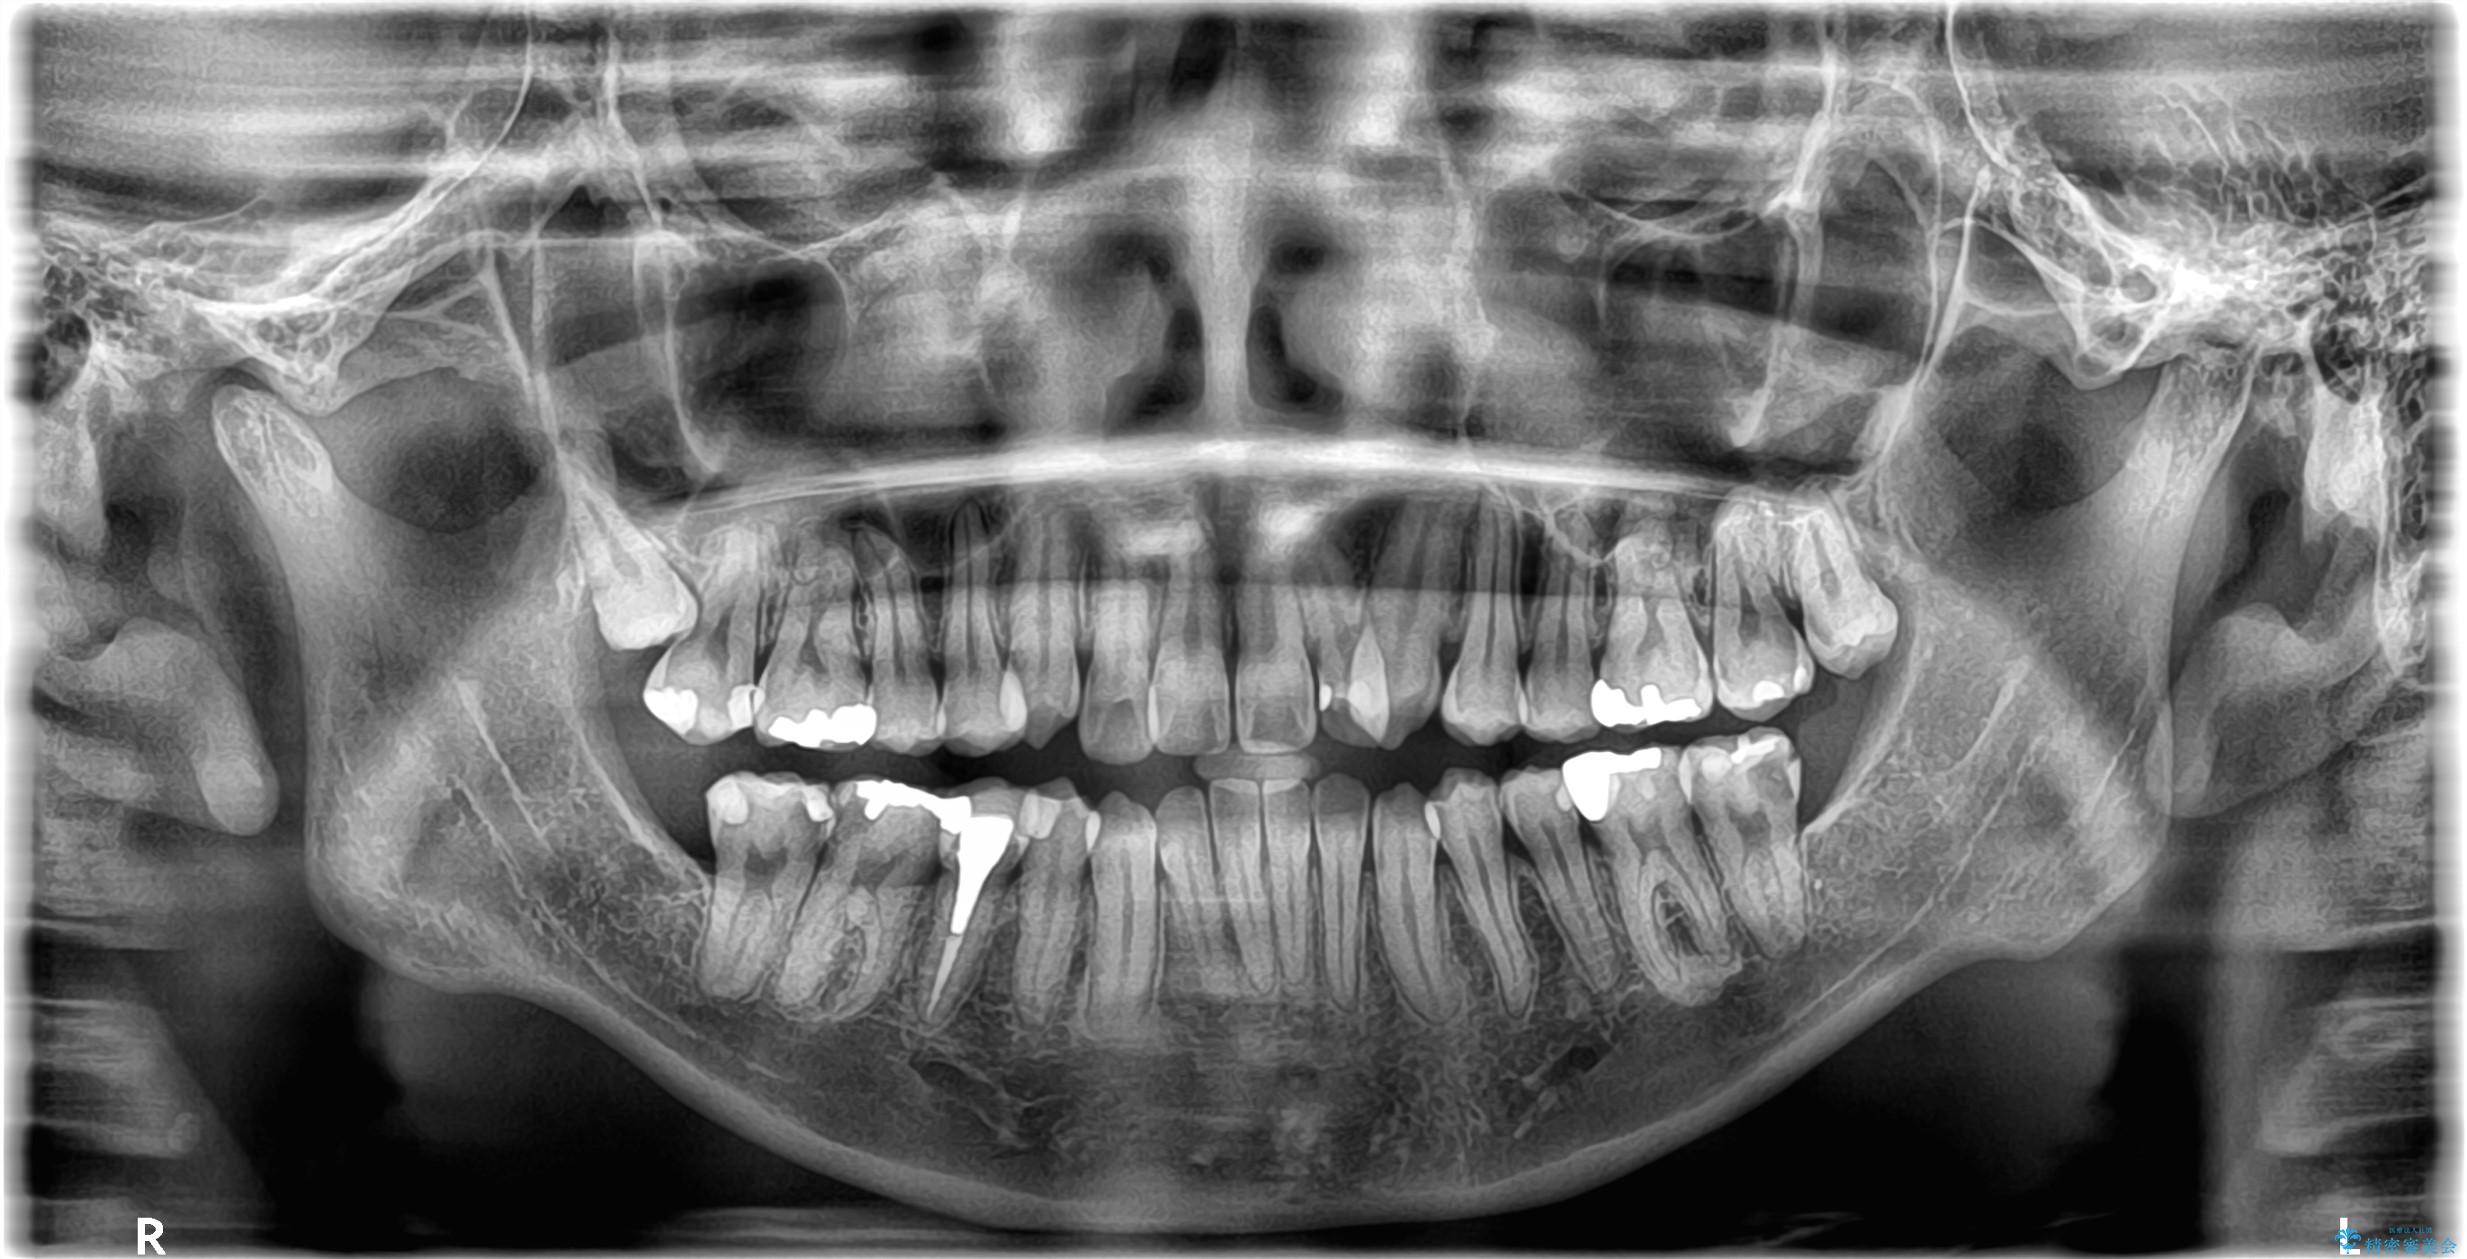

- 開咬と歯のデコボコ(叢生)、八重歯を主訴にご来院された患者様です。

矯正の精密検査の結果、上顎左右4番および下顎左右5番の計4本を抜歯し、ワイヤー矯正(クリア装置)にて治療を行いました。

虫歯があったので、虫歯治療は矯正前に行っています。